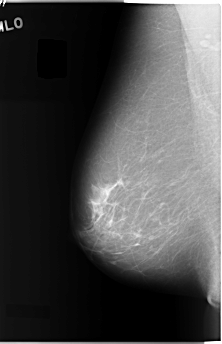

C_0040_1.RIGHT_MLO

RIGHT_MLO LINES 5840 PIXELS_PER_LINE 3760 BITS_PER_PIXEL 12 RESOLUTION 50 NON_OVERLAY